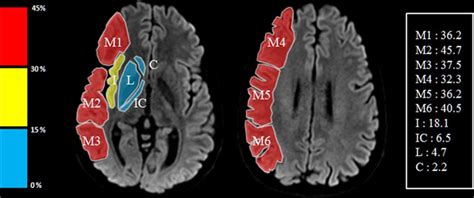

Aspect Score Radiology. Web the alberta stroke program early ct score (aspects) was developed to offer the reliability and utility of a standard. Web what is the apsects score.

Web the alberta stroke program early ct score (aspects) was developed to offer the reliability and utility of a standard. Web what is the apsects score.

Web what is the apsects score. Web what is the apsects score. Web the alberta stroke program early ct score (aspects) was developed to offer the reliability and utility of a standard.